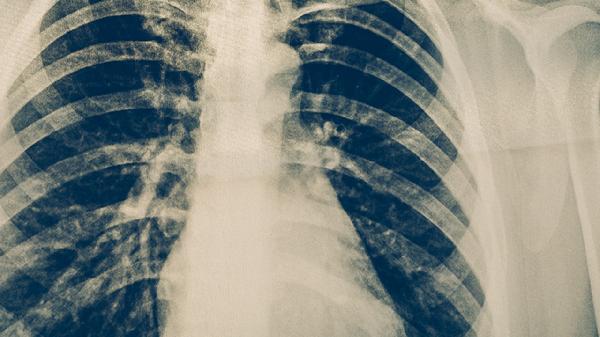

肺結核治療需遵循早期、聯(lián)合、適量、規(guī)律、全程原則,常用藥物包括異煙肼片、利福平膠囊、吡嗪酰胺片、乙胺丁醇片和鏈霉素注射液等。肺結核是由結核分枝桿菌感染引起的慢性傳染病,需在醫(yī)生指導下規(guī)范用藥。

確診后應立即開始抗結核治療,早期用藥可有效殺滅活躍繁殖的結核菌,減少肺組織損傷。延誤治療可能導致病灶擴散或形成空洞,增加治療難度。常用藥物如異煙肼片對繁殖期結核菌有強殺菌作用,需與其他藥物聯(lián)用。

肺結核患者應保持均衡飲食,適當增加優(yōu)質蛋白和維生素攝入,避免辛辣刺激性食物。注意居室通風消毒,佩戴口罩防止傳播,定期復查胸部影像學和痰菌檢查。出現(xiàn)藥物不良反應如皮疹、黃疸時應及時就醫(yī),治療期間禁止飲酒。適當進行呼吸功能鍛煉有助于肺組織修復,但需避免劇烈運動。